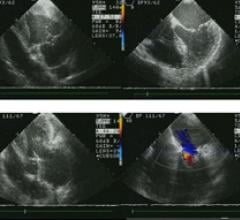

This channel includes news and new technology innovations about cardiovascular ultrasounds. Cardiovascular ultrasounds, or echocardiograms, use ultrasound imaging to provide a picture of the heart.